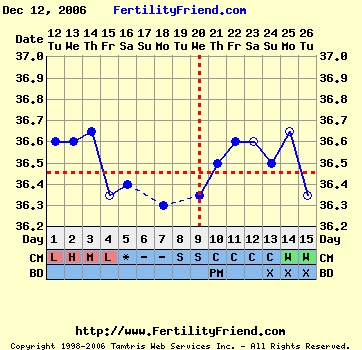

Nem tudom, hogy ez normális-e, miközben minden hormonom rendben, és a hőgörbe mutat pé-t. Meg van pozitív LH tesztem is...

Gaby: a Te görbéd elég cikkcakkos, szerintem később pé-zel...Végülis hathatott a párodnál már a gyógyszer, ha nem is drasztikusan, de már jobbak lehetnek az eredményei...